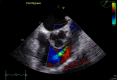

Decision-Making in a Pulmonary Valve Fibroelastoma: The Role of Intraoperative Transesophageal Echocardiography

Keywords: Cardiac fibroelastoma; Cardiac surgery; Cardiac tumor; Pulmonary valve; Transesophageal echocardiography.